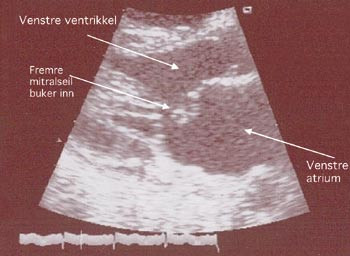

Røntgen thorax viste ikke nytilkommede forandringer på lunger eller mediastinum, men transtorakal ekkokardiografi viste moderate mengder perikardvæske uten truende tamponade, mitralinsuffisiens grad 3 av 4 (fig 2), ca. 50 mm Hg systolisk pulmonalarterietrykk og moderat trikuspidalinsuffisiens. Undersøkelsen ble gjentatt dag 5, og viste da ytterligere forverret hemodynamikk.

Dag 12 ble han operert pga. økende perikardvæske, truende tamponade, høyt lungekartrykk, trikuspidalinsuffisiens og begynnende nyresvikt. Peroperativt var perikard struttende av blodig serøs væske uten koagler, og det var vanskelig å kjenne hjertets pulsasjon. Hjertet og de store kar var dekket med fibrin. Eksponering av mitralapparatet avdekket en forlenget og avbleket fremre papillemuskel. Chordaapparatet var nesten intakt, men fremre mitralseil og koaptasjonsflaten mot bakre seil var trukket inn i atriet. Morfologisk var dette forenlig med en avaskulær papille- og ventrikkelmuskulatur. Hele klaffeapparatet ble bevart og en mekanisk ventil (Carbomedics 27 mm) ble implantert.